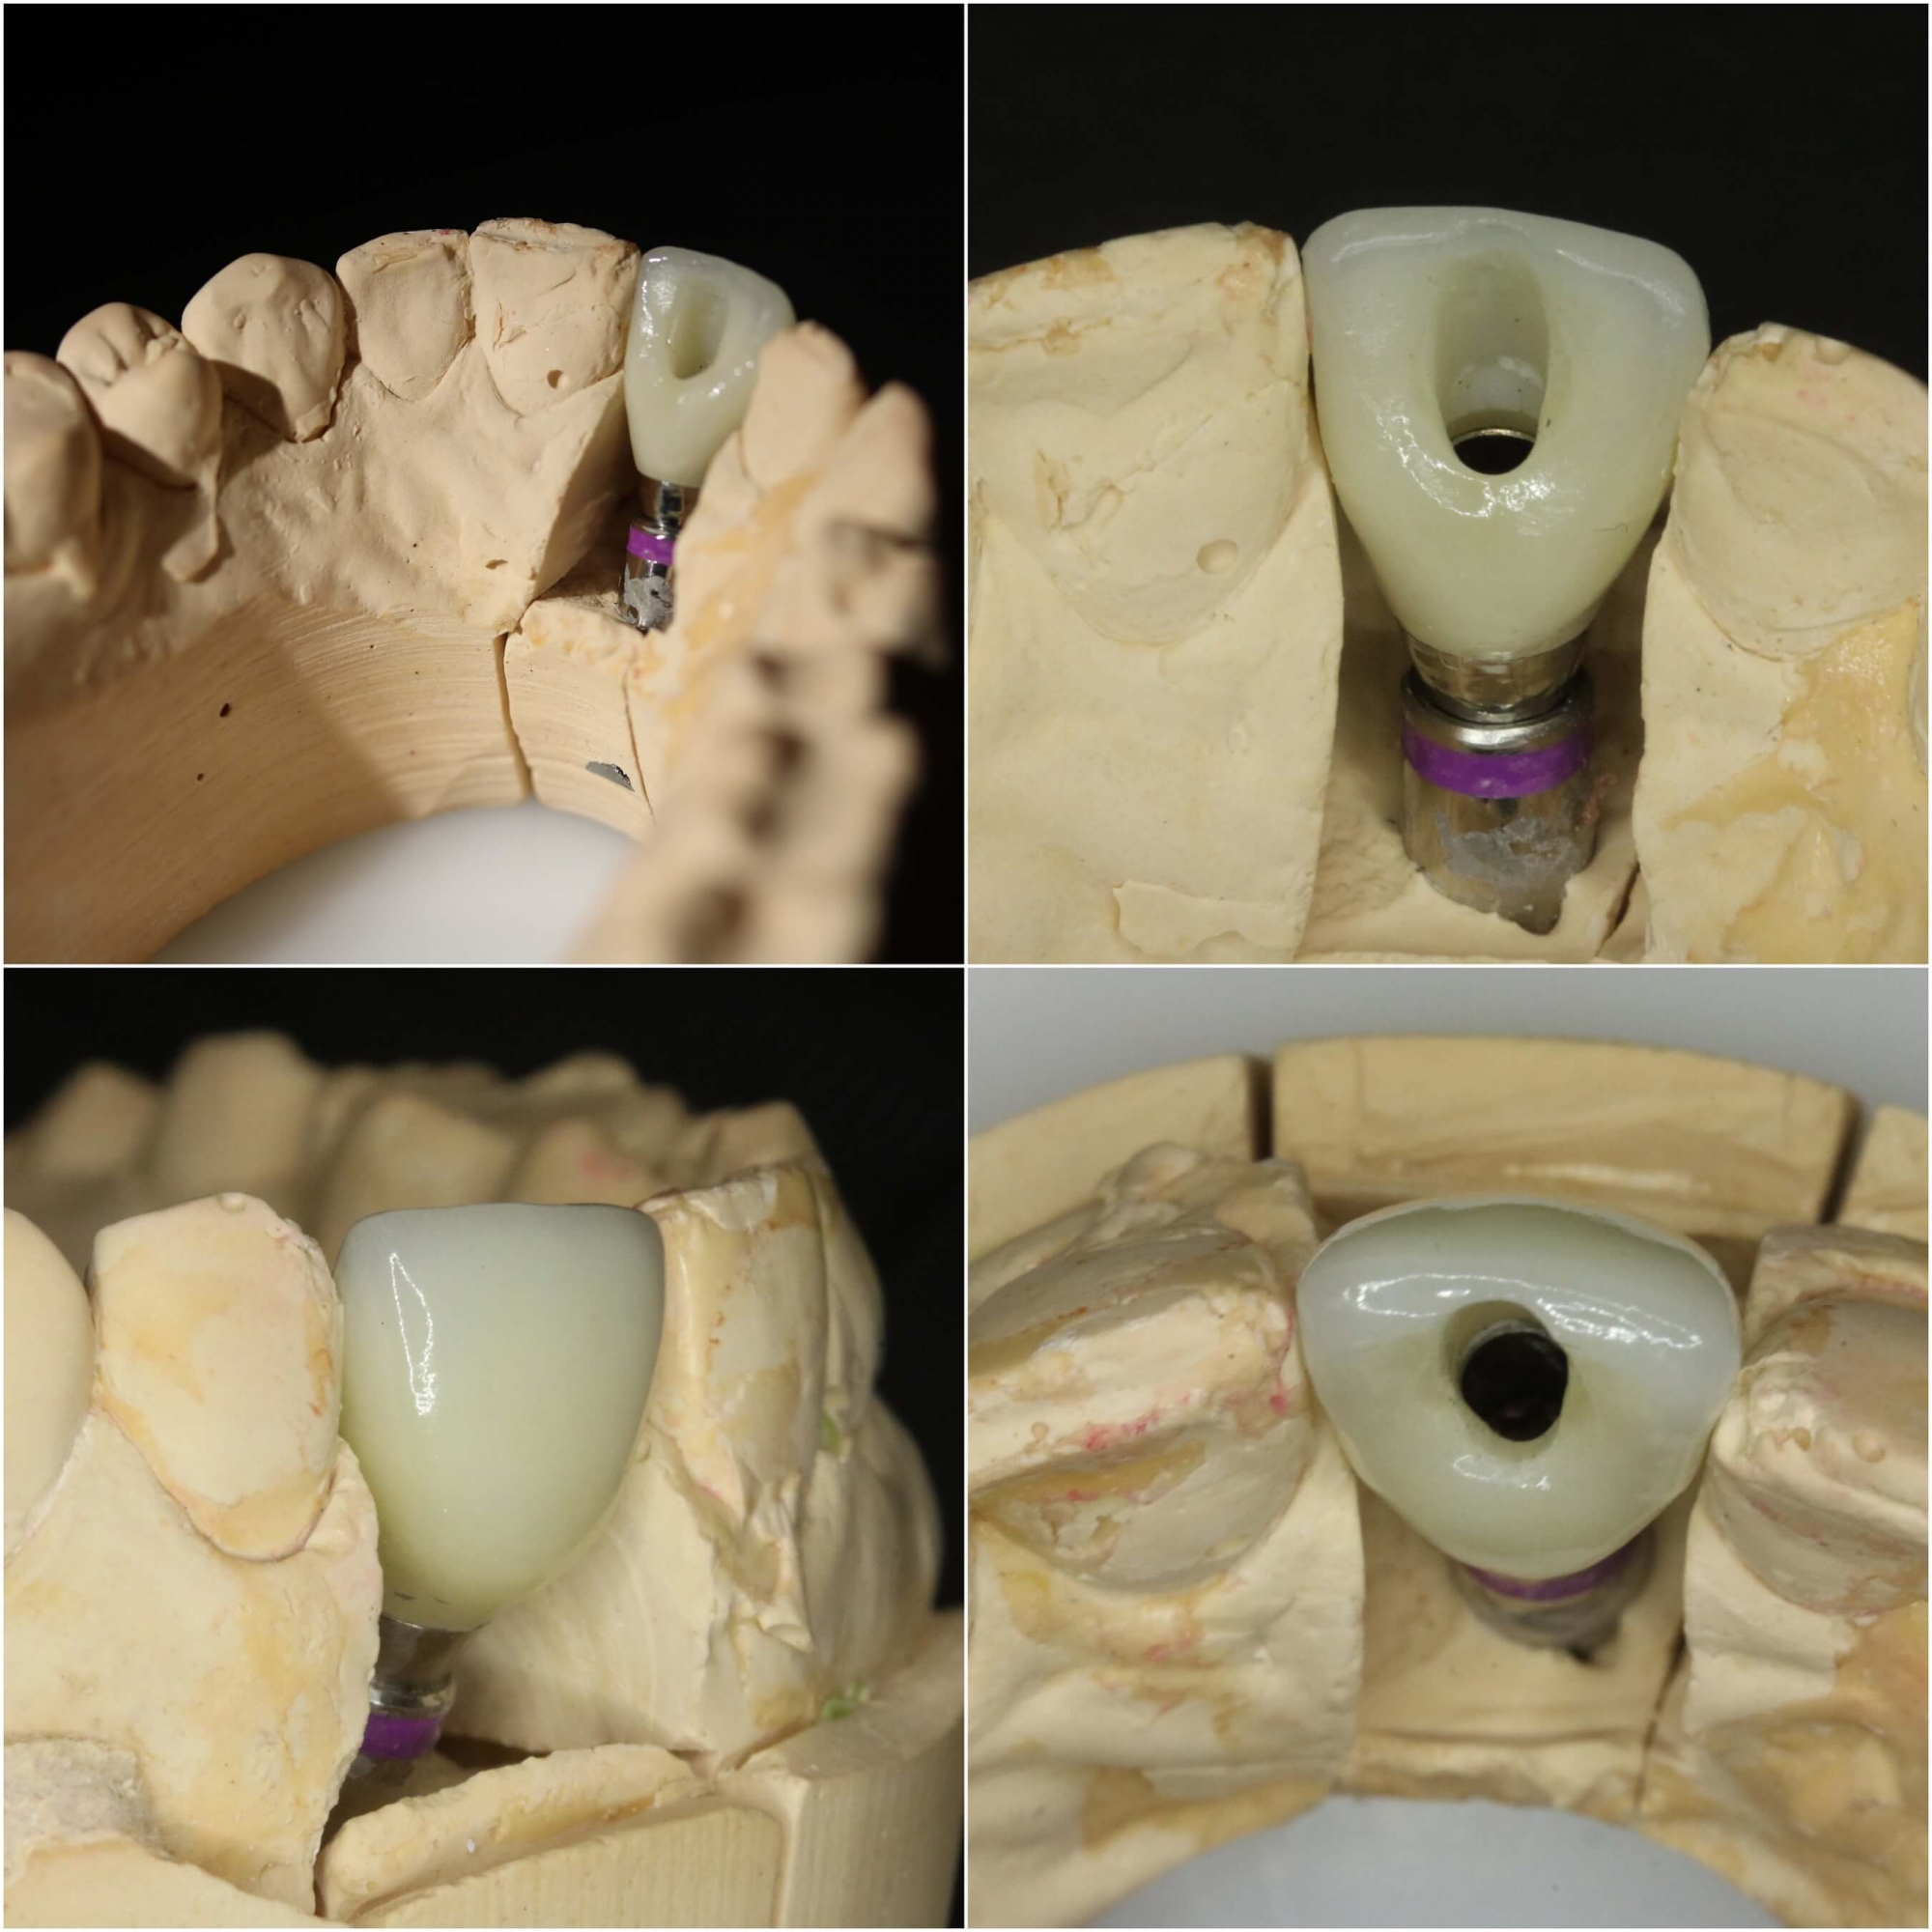

• Tūlītēja zoba implanta ievietošana un pagaidu kronīša (plastmasa) izgatavošana.

• Pēc 5 mēnešiem tika izgatavots slāņots cirkonijkeramikas kronis